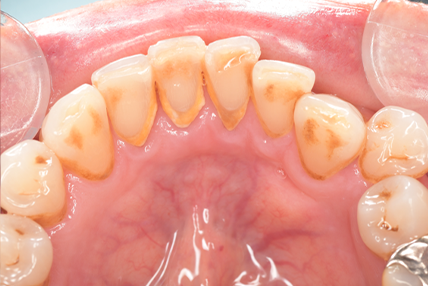

CASE 5

Before

After

基本情報

| 年齢・性別 | 19歳・女性 |

|---|---|

| 主訴 | 定期検診 |

| 治療内容 | PMTC |

| 治療期間 | 30分 |

| 治療費 | 5,500円 |

| リスク・副作用 | 知覚過敏 |

| 治療方針 | スケーリングしてから着色を除去しました。着色は一度綺麗に落としても再度付着するため、今後は定期的なクリーニングを行います。 |

| 担当者所見 | 歯ぐきに色素が沈着しているためガムピーリングとホワイトニングを行うことで、より明るく見えるようになります。 |